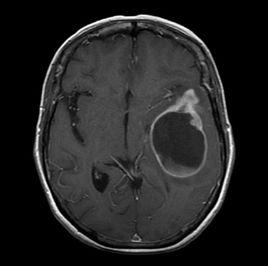

臨床表現多為頭痛、抽搐及精神症狀等,腫瘤生長迅速,高度惡性,病情進展一般較快,平均存活期約12個月。GBM的細胞學特點為瘤組織內見到明顯壞死灶,周圍瘤細胞呈柵欄狀排列,間質內小血管明顯增生呈花蕾狀、腎小球樣,或形成彎曲長帶狀,瘤細胞常呈多形性,易見異形多核巨細胞,習慣上常稱為多形性膠質母細胞瘤。免疫組化標記常以GFAP(+)為基礎,波形蛋白(Vimentin)(+)多提示瘤細胞分化較差,EMA、細胞因子(CK)(+)多提示瘤細胞上皮樣化生。GBM主要位於大腦半球的白質內,常侵犯額、顳、頂葉,枕葉較少見,基底節和胼胝體常受累,瘤組織可以經胼胝體侵犯對側大腦半球呈S形生長,或是經胼胝體在兩側大腦半球深部呈蝶形生長,丘腦的GBM也不少見。小兒和青年人的腦幹膠質瘤大多轉變為GBM,小腦內GBM十分少見。由於腫瘤細胞高度間變和不成熟性、新生血管結構不良、血栓形成等原因,所以常有廣泛退變出血和壞死,因此腫瘤具有多形性的特徵。

GBM的生長特性:①可沿白質中的神經束伸展至深處,例如額葉腫瘤可沿額頂束生長至同側頂葉,沿鉤束生長至同側顳葉,甚至可沿胼胝體生長至對側大腦半球;②多中心性生長,有4.9%~20%的GBM由幾個似乎獨立的瘤中心組成,各個瘤中心常聚集在一起,有時在腫瘤主體附近可見衛星灶。